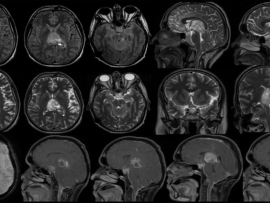

A term, appropriate-for-gestational-age neonate with normal APGAR scores and no history of perinatal hypoxia presented with seizures on day 2 of life.